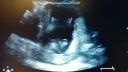

Toto je Adamko na 4D koniec 21. týždeň tehotenstva.